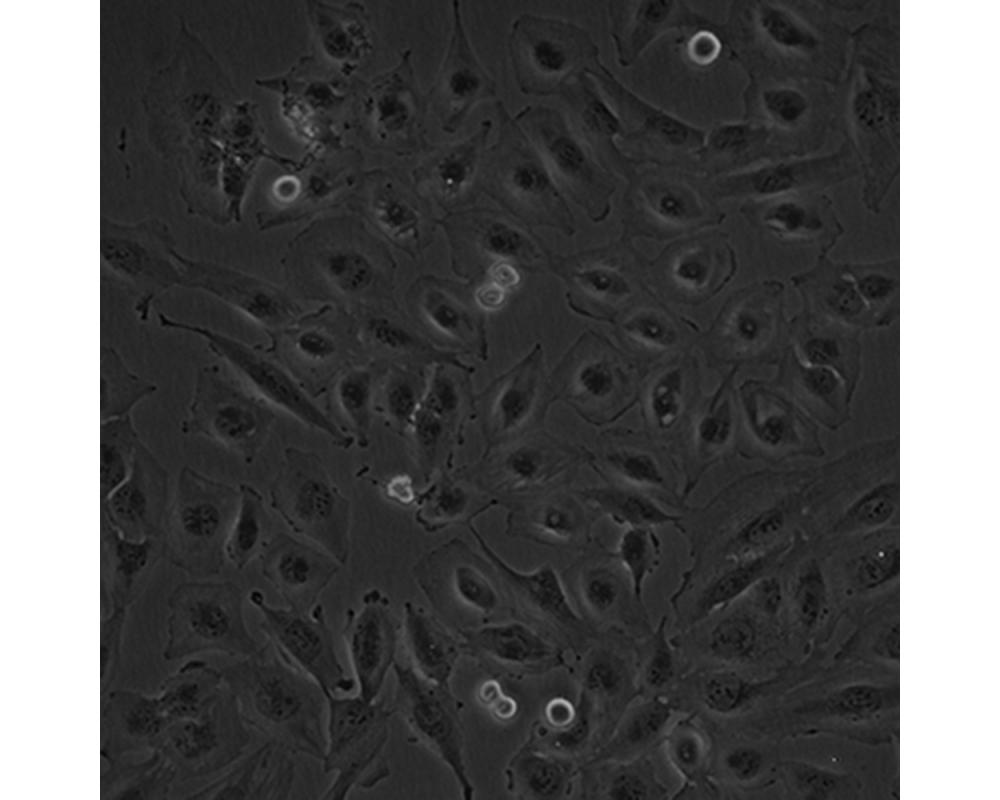

中文名稱 人腦髓母細(xì)胞瘤細(xì)胞

組織來源 成神經(jīng)管細(xì)胞瘤;男性

形態(tài)特征 多邊形

生長特性 貼壁生長

特征特性 該細(xì)胞是1985年由Jacobsen PF建立的,源自一名4歲大的兒童的后顱窩腫瘤的活檢組織,未檢出神經(jīng)元和膠質(zhì)分化的特征;可用作轉(zhuǎn)染宿主。

培養(yǎng)條件 DMEM+10%FBS

傳代方法 1:4~1:6傳代;每周換液2~3次。